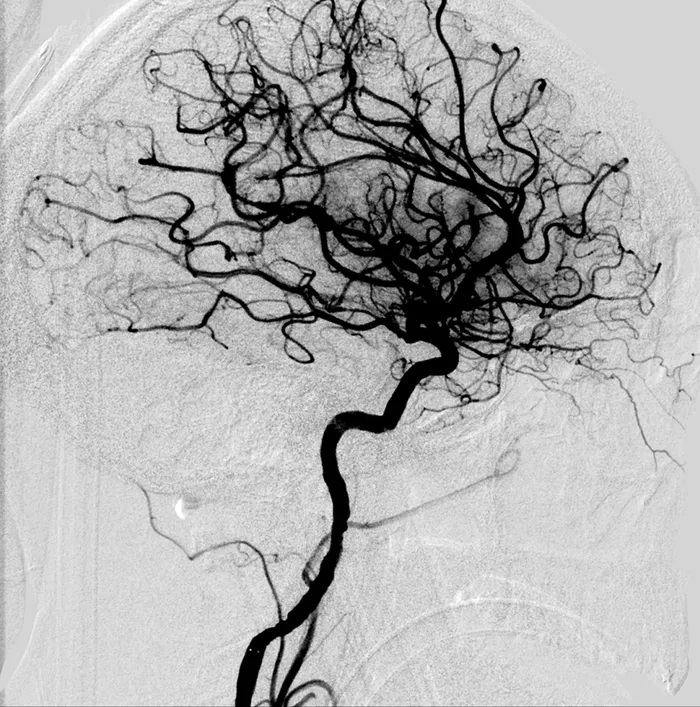

Behind every successful stroke recovery is the power of imaging technology. Neuroimaging allows doctors to quickly determine the type of stroke and the best course of action.

Radiologists play a pivotal role in stroke care, ensuring patients get the right treatment, whether it’s a clot-busting drug or surgery.